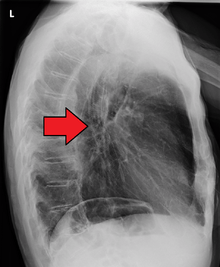

If the cancer has spread elsewhere, symptoms related to metastatic disease may appear. Common sites of spread include nearby lymph nodes, the liver, lungs and bone.[12] Liver metastasis can cause jaundice and abdominal swelling (ascites). Lung metastasis can cause, among other symptoms, impaired breathing due to excess fluid around the lungs (pleural effusion), and dyspnea (the feelings often associated with impaired breathing).

Additional testing is needed to assess how much the cancer has spread (see #Staging, below). Computed tomography (CT) of the chest, abdomen and pelvis can evaluate whether the cancer has spread to adjacent tissues or distant organs (especially liver and lymph nodes). The sensitivity of a CT scan is limited by its ability to detect masses (e.g. enlarged lymph nodes or involved organs) generally larger than 1 cm. Positron emission tomography is also used to estimate the extent of the disease and is regarded as more precise than CT alone. Esophageal endoscopic ultrasound can provide staging information regarding the level of tumor invasion, and possible spread to regional lymph nodes.